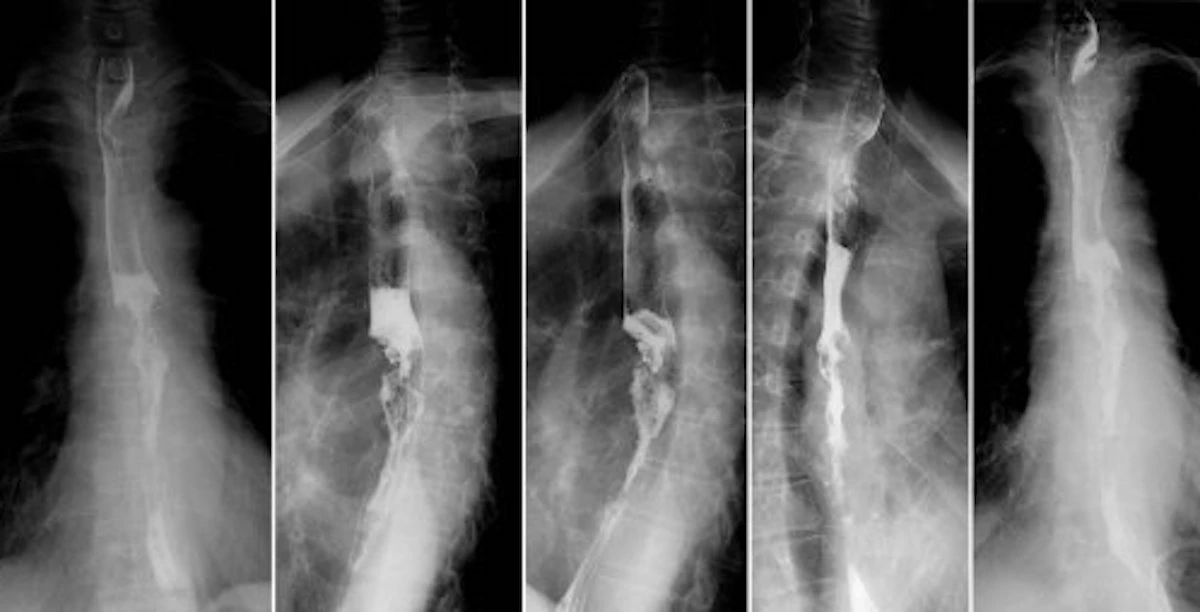

Tra gli esami più utili ci sono la gastroscopia, che permette di osservare direttamente l’esofago e lo stomaco, e test funzionali come la manometria esofagea e la pH impedenziometria, fondamentali per valutare la funzionalità dello sfintere e la quantità di acido che risale.